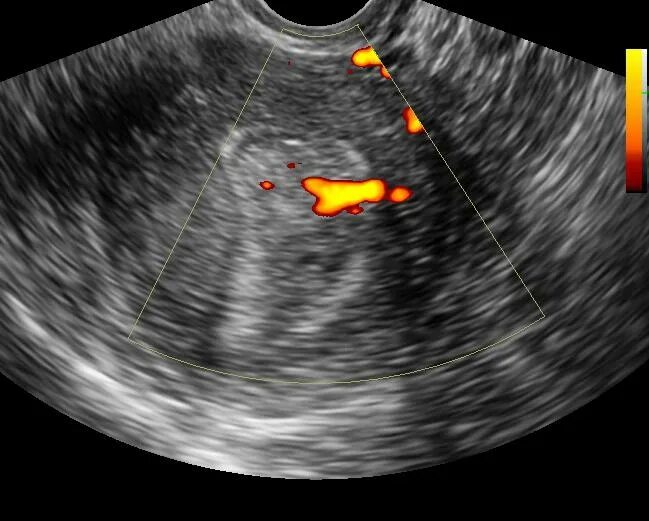

Удалить полип матки лазером